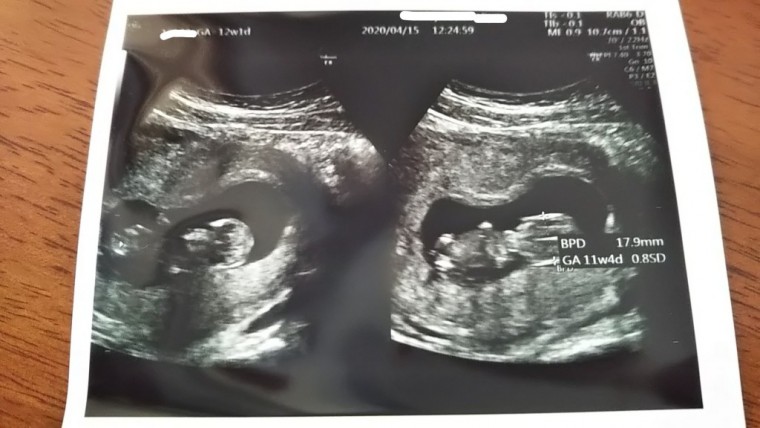

妊娠4ヶ月 12週1日 撮影日:2020年04月15日

画面に映された瞬間の衝撃といったら!

((えっ、なにこれ(*゜Q゜*)!?

すごっ❗️))

ちゃんと動いてて

小さく跳ねてた

小さい人形のような

ちゃんと人形になっていて感動